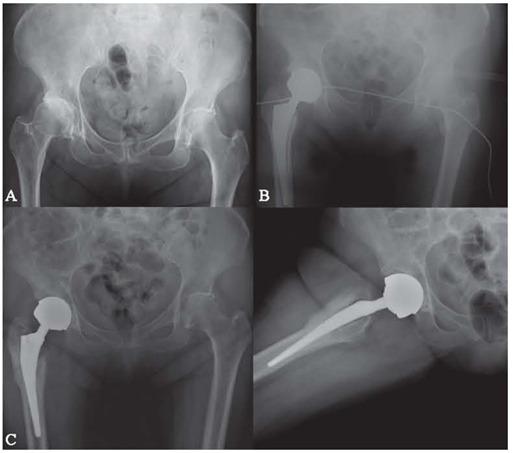

Adverse reaction to metal debris is the major cause of the high revision rates of metal on metal hip implants with femoral head size ≥ 36mm. Health authorities recommend regular surveillance even for asymptomatic individuals. The main investigations used are Co+ and Cr+ serum levels, x-rays and, eventually, ultrasound and MARS-MRI. Clinic is also assessed. The aim of this study is to identify if there is a relation between  ion levels and the clinical scores  in order to evaluate the outcome and  plan the correct management after this type of implant.

金属颗粒导致的不良反应是 36mm 以上金属对金属髋关节植入物高返修率的主要原因。健康机构建议对无症状人群进行定期监测。主要检查手段包括 Co+ 和 Cr+ 血清水平、X 射线,以及最终的超声和 MARS-MRI。同时也会进行临床评估。本研究旨在确定离子水平与临床评分之间是否存在关联,以便评估结果并为这类植入物的后续管理制定正确的方案。